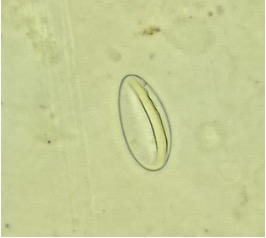

Ovo de Trichuris trichiura

Ovos de Trichuris trichiura